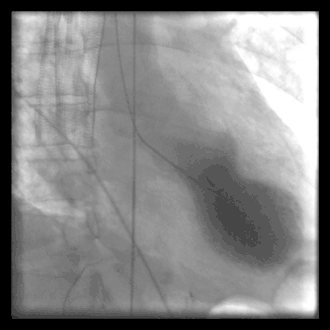

Left ventriculography during systole showing apical ballooning akinesis with basal hyperkinesis in a patient with takotsubo cardiomyopathy.